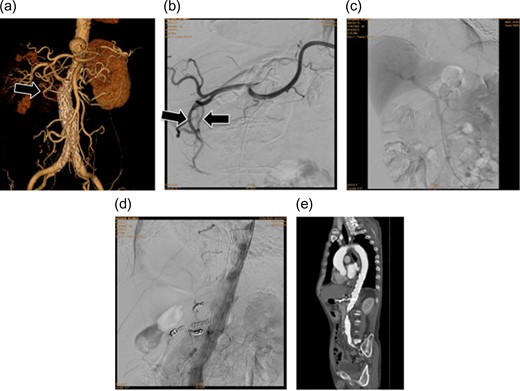

(a) Preoperative three-dimensional computed tomography (3D-CT) angiography showing the aneurysm. An arcade for the celiac and superior mesenteric arteries was confirmed via the gastroduodenal artery (arrow). (b) Intraoperative image of the celiac artery. As on the 3D-CT images, an arcade via the gastroduodenal artery was confirmed (arrow). (c) Portal phase image of the SMA. The liver is imaged during blood flow from the portal vein, confirming that the liver will be supplied with blood even if the hepatic artery blood flow decreases. (d) Angiography after placing the stent graft. No endoleaks, including Type II endoleaks from the celiac artery, are observed. Accordingly, the treatment was deemed effective. (e) Postoperative contrast-enhanced CT. No endoleaks are observed, so the treatment was considered successful.